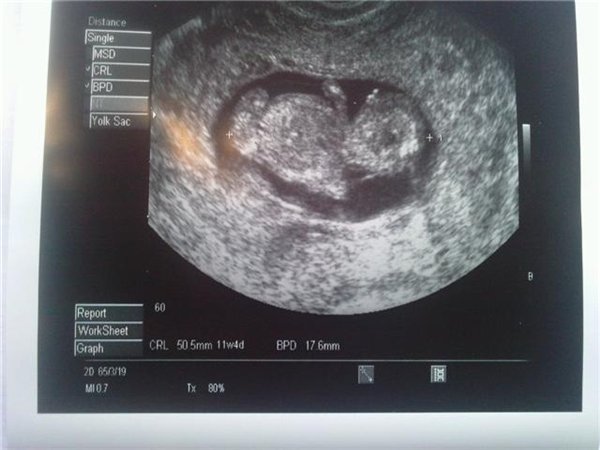

er 11+4 efter hendes scanningen i dag og skal bare lige tag de sidste 5 progestron 2 i dag 3 i morgen så er det også afslutte...

HER ER VORES BABY.......